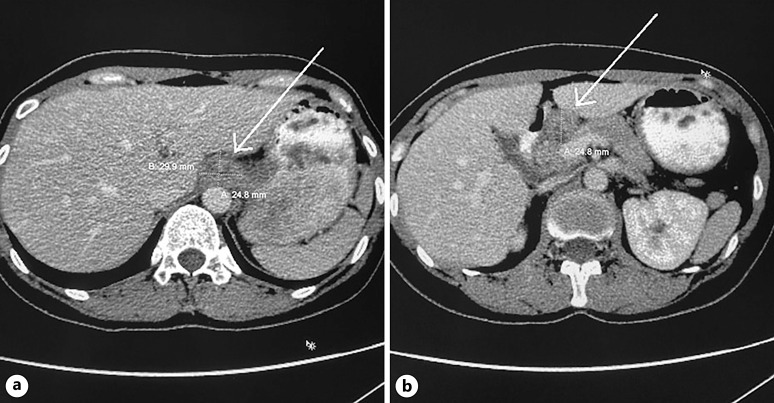

Case presentation: We report a unique case of a 37-year-old woman who presented with dysphagia secondary to esophageal TB with an endoscopic appearance of a submucosal mass resembling malignancy.